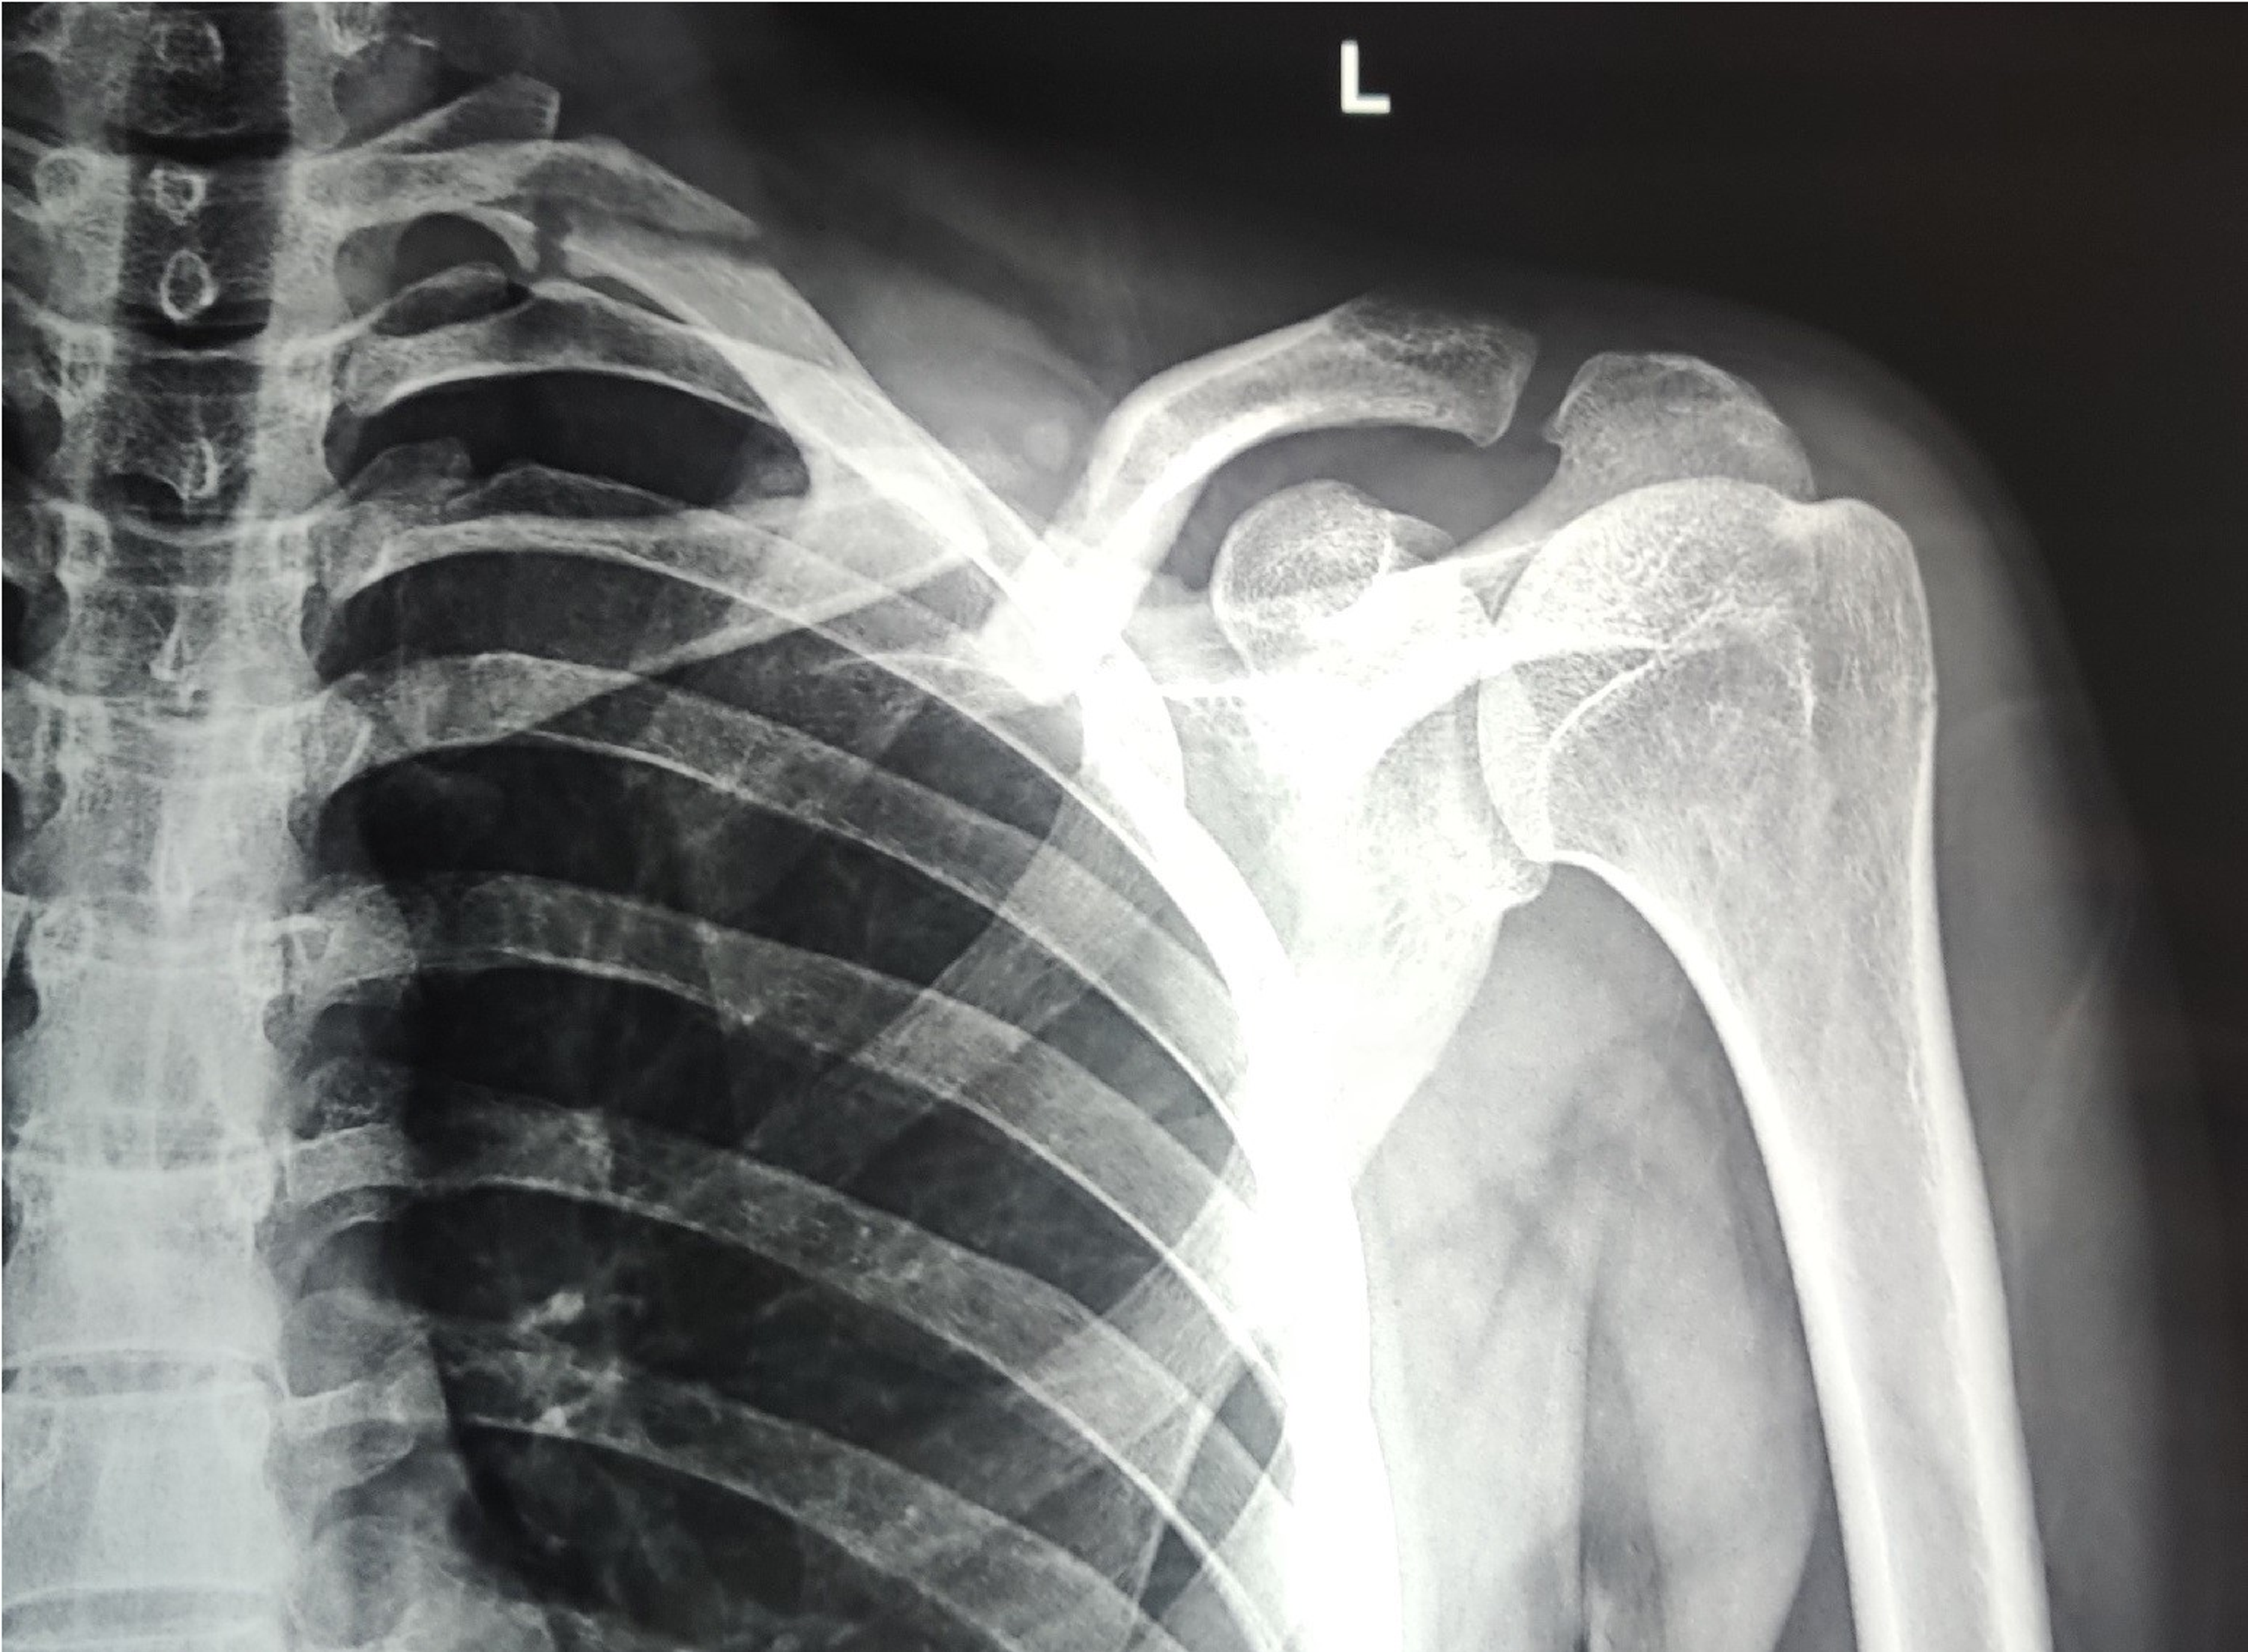

Beach Chair Position Clavicle Surgery And Children. Upright x-rays of the patient will help to determine the true displacement and shortening of the fracture. Techniques in Shoulder and Elbow Surgery.